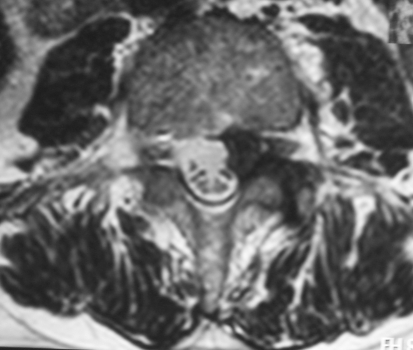

A lumbo-sacral (L1–S1) CT scan showed an inhomogeneous hypodense formation at the level of right L3–L4 neuroforamen. The patient underwent MRI which revealed a bilobar mass between L3 and L4, suggesting a lumbar Schwannoma extending to the right ipsilateral foramen (Figs. 1, 2).

Fig. 2.

Case 1, sagittal preoperative T1 MRI sequence